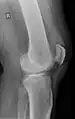

An x-ray demonstrating quadriceps tendon rupture. Note the abnormal angle of the patella and soft-tissue swelling marked by the arrow.

A quadriceps tendon rupture is a tear of the tendon that runs from the quadriceps muscle to the top of the knee cap.[1]